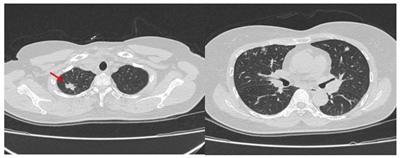

CA LÂM SÀNG:  ĐIỀU TRỊ BỆNH NHÂN UNG THƯ PHỔI KHÔNG CÒN CHỈ ĐỊNH PHẪU THUẬT TẠI TRUNG TÂM Y HỌC HẠT NHÂN VÀ UNG BƯỚU, BỆNH VIỆN BẠCH MAI

Ngày đăng: 15/07/2025

Theo GLOBOCAN 2022, trên thế giới, ung thư phổi đứng đầu về số ca mới mắc (với gần 2,5 triệu ca, chiếm 12,4% tổng số ca mới mắc) và đứng đầu về tỷ lệ tử vong (với 1,8 triệu ca, chiếm 18,7% tổng số ca...